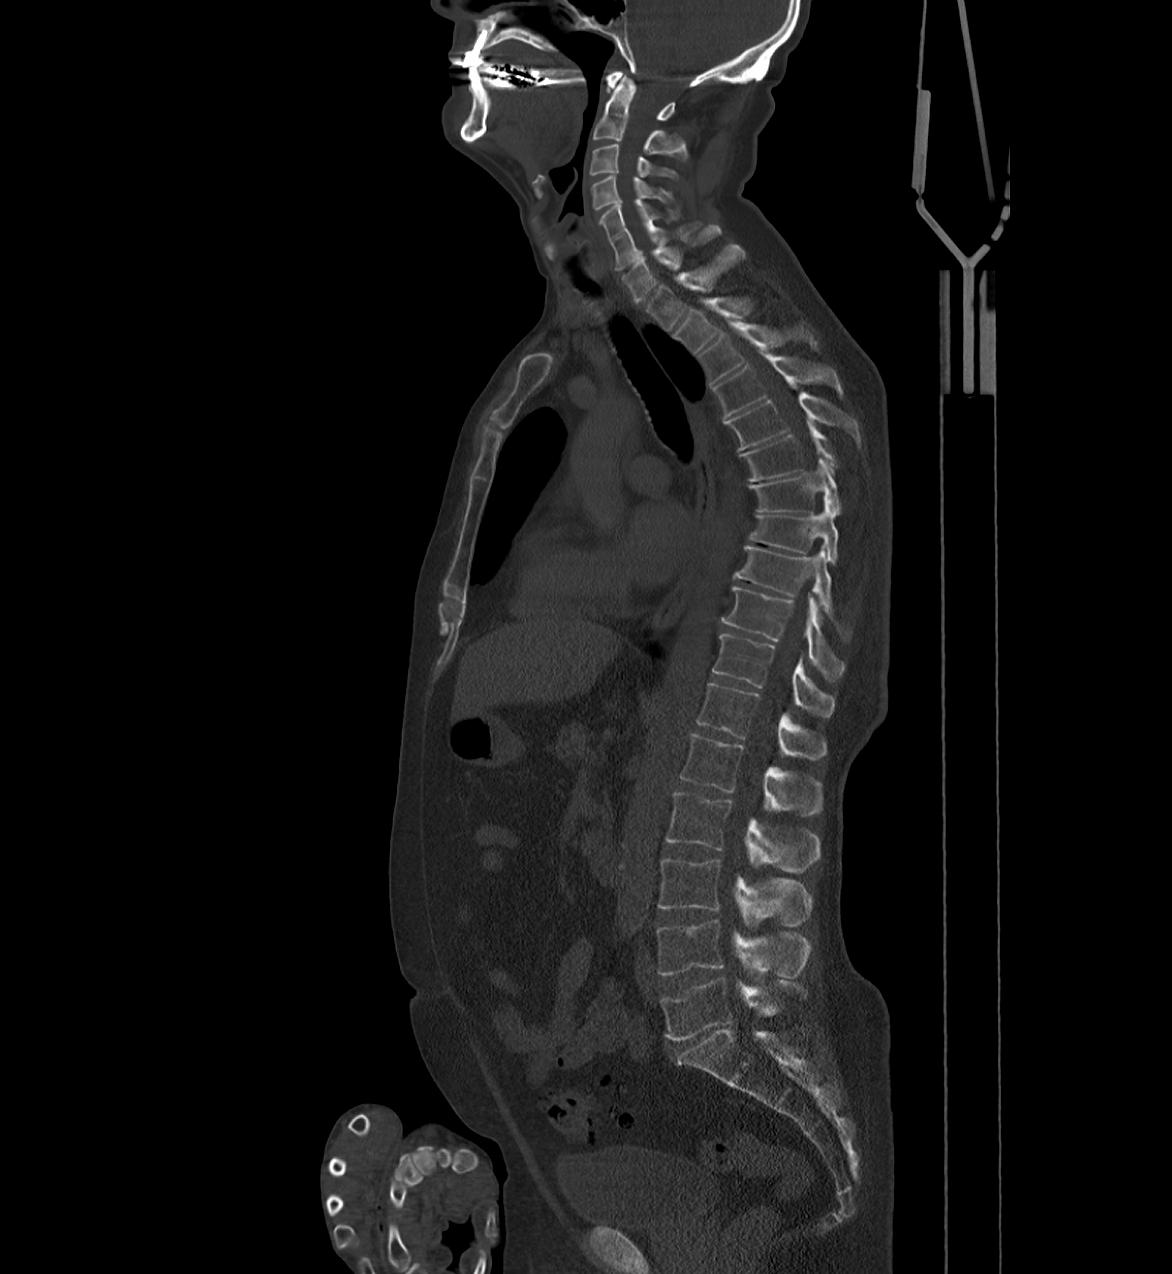

Die Kernspintomographie (Magnetresonanztomographie ( MRT), NMR) erzeugt, ähnlich der Computertomographie Schnittbilder des menschlichen Körpers. Sie benötigt im Gegensatz zu der Computertomographie keine Röntgenstrahlen, sondern lediglich ein starkes Magnetfeld und Radiowellen. Das physikalische Prinzip ist schon seit 1946 bekannt, seit Beginn der 80er Jahre wird es auch als diagnostisches Verfahren in der Medizin verwendet.

Atomkerne besitzen eine spezielle physikalische Eigenschaft, die als Kernspin bezeichnet wird. In der MRT werden die "magnetischen" Drehachsen der Wasserstoffkerne des Körpers durch ein sehr starkes Magnetfeld ausgerichtet. Mit Hilfe von Radiowellen mit einer genau definierten Frequenz, der sog. Resonanzfrequenz lassen sich die ausgerichteten Wasserstoffkerne selektiv beeinflussen. Das MRT Signal eines bestimmten Gewebes wird hauptsächlich durch den Gehalt an Wasserstoffkernen sowie den speziellen chemischen und physikalischen Eigenschaften des Gewebes geprägt.

Viele Teile des menschlichen Körpers (zum Beispiel Knorpel, Sehnen, Bindegewebe und Muskulatur oder auch unterschiedliche Gebiete des Gehirns) weisen nur sehr geringe Dichteunterschiede auf und lassen sich deshalb mit der Computertomographie nur ungenügend voneinander unterscheiden. Unter anderem durch ihren unterschiedlichen Gehalt an Wasserstoffkernen lassen sich diese Gewebe in der MRT jedoch sehr gut beurteilen. Die Möglichkeiten der MRT gehen jedoch weit über die "einfache" Darstellung von Körperregionen hinaus. Die kontinuierliche Weiterentwicklung der MRT-Technik erschließt ständig neue Einsatzmöglichkeiten, eine vollständige Beschreibung aller Anwendungsmöglich-keiten würde den Rahmen dieser Seiten bei weitem sprengen! Hingewiesen werde soll auf die besondere Bedeutung der Diffusionsgewichten Sequenz für die frühe Schlaganfalldiagnostik und die Charakterisierung tumoröser Raumforderungen und die nicht-invasive Gefäßdarstellung, die sog. MR-Angiographie.

Der Vorteil der MRT aus medizinischer Sicht liegt nicht nur in der hohen Qualität der Weichteildarstellung, sondern auch in der Tatsache, daß ohne Umlagerung des Patienten jede beliebige "Schnittebene" dargestellt werden kann und das Verfahren ohne Röntgenstrahlung auskommt.